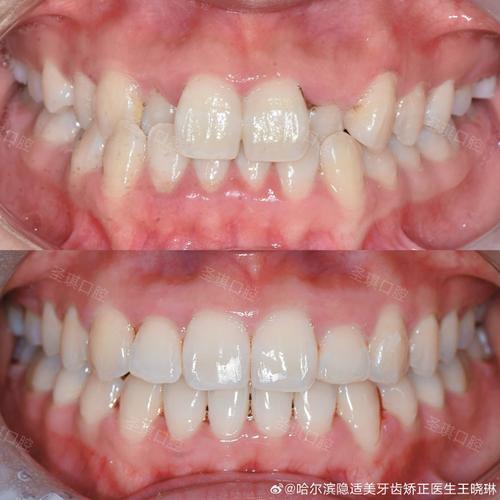

保持与随访

矫治完成后,拆除矫治器,佩戴保持器(如 Hawley 保持器、透明压膜保持器或固定式保持丝),防止后牙复发,保持时间通常为6-12个月,期间每3个月复诊一次,评估咬合稳定性及牙周健康状况。

(图片来源网络,侵删)